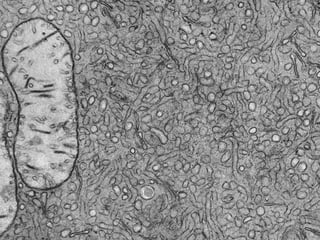

Este documento presenta imágenes microscópicas de diferentes tipos de tejidos y estructuras celulares teñidas con varios métodos histológicos. Incluye fotografías que muestran fibras de colágeno, elásticas y reticulares en diversos órganos, así como membranas basales y células especializadas de órganos como riñones, glándulas mamarias y próstata. El propósito es demostrar la aplicación de técnicas histológicas para visualizar componentes celulares y tej